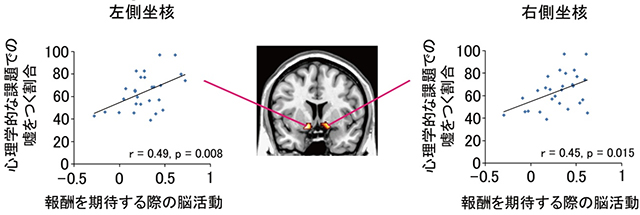

その結果、報酬(今回の研究ではお金)を期待する際の「側坐核(そくざかく)」と呼ばれる脳領域の活動が高い人ほど、嘘をつく割合が高いことがわかりました(図)。さらに、側坐核の活動が高い人ほど、嘘をつかずに正直な振る舞いをする際に、「背外側前頭前野(はいがいそくぜんとうぜんや)」と呼ばれる領域の活動が高いこともわかりました。

図:報酬期待に関わる側坐核の反応と、嘘をつく割合との正の相関(論文中のFigure2を改変)